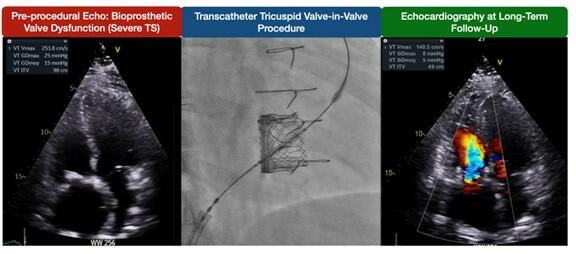

Two patients developed bioprosthetic valve dysfunction, classified as major late device dysfunction according to TVARC. The first case involved severe TR with an elevated mean gradient 3 years after the procedure; however, the patient remained in good functional class, and no reintervention was planned at the last follow-up. The second case was a patient who later died from methadone overdose. This patient developed significant tricuspid stenosis (mean gradient >10 mm Hg) at 14 months and was maintained on dual antiplatelet therapy (DAPT) during follow-up. No reintervention was planned, likely because the patient’s symptoms remained stable.

Data on TR severity during follow-up are shown in Figure 1B. At baseline, 33.3% (4) of patients had severe TR, 25% (3) had moderate TR, 8.3% (1) had mild TR, and 33.3% (4) had no or trace TR. At 1 month, all patients had no or trace TR (P = .04). During follow-up, 1 patient developed severe TR at the third year, classified as device dysfunction according to TVARC. However, this patient remained in NYHA class II and did not undergo tricuspid reintervention at the last follow-up. Figure 2 illustrates a case with sustained gradient improvement and no residual TR.